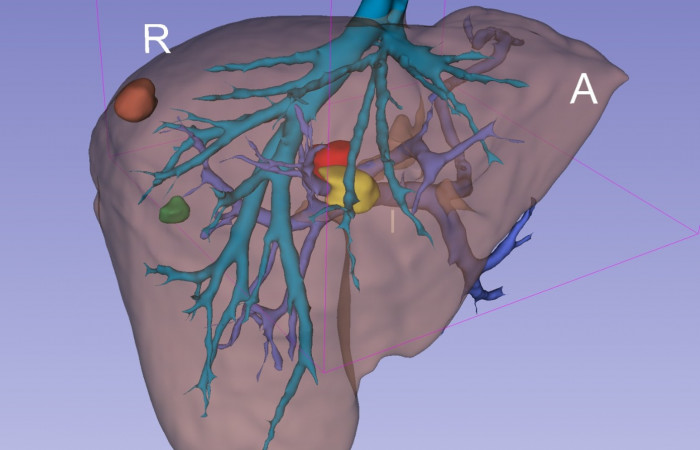

Pracownia Funkcjonalnego i Wirtualnego Medycznego Obrazowania 3D

(ang. Laboratory of Functional and Virtual Medical 3D Imaging, akronim: 3D-vFMi(maging), skrót: 3D-FM)

Pracownia Funkcjonalnego i Wirtualnego Medycznego Obrazowania 3D (Pracownia 3D-FM) funkcjonuje w strukturze Zakładu Diagnostyki Obrazowej Szpitala Uniwersyteckiego w Krakowie pod kierownictwem Prof. dr hab. Tadeusza Popieli. Jej celem jest opracowanie i wdrożenie innowacyjnych metod przetwarzania oraz analizy sygnałów i obrazów medycznych, w tym wykorzystanie technologii rzeczywistości wirtualnej oraz metod obrazowania funkcjonalnego. Rozwiązania te wspierają przedoperacyjne planowanie, monitorowanie procedur medycznych oraz wzbogacają proces diagnostyczny o nowe formy wizualizacji danych medycznych.

Pracownia 3D-FM zajmuje się m.in. następującymi obszarami:

- Tworzeniem modeli 3D do celów przedoperacyjnego planowania oraz wizualizacji diagnostycznej.

- Obrazowanie Medyczne 3D

- Segmentacja i analiza danych DICOM

- Rekonstrukcja danych medycznych